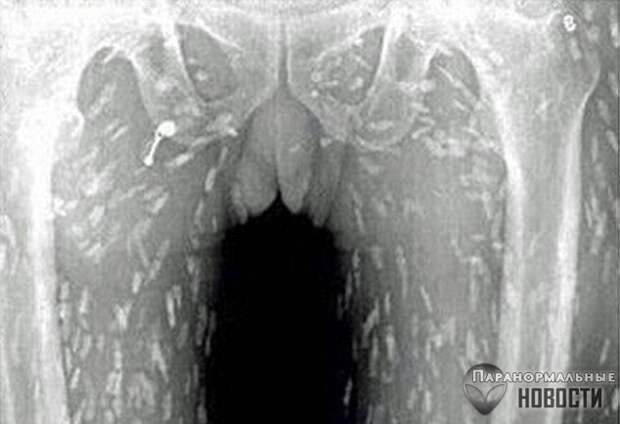

Житель провинции Гуандун обратился в больницу с жалобами на боли в животе - и рентген показал, что все его органы буквально оккупированы червями-солитерами.

Врачи считают,что причиной этого стало увлечение мужчины суши, он постоянно ел их с сырой рыбой. Червей в его организме было так много, что первым его порывом, когда он увидел на рентгене копошащуюся армию паразитов внутри себя, было сигануть из окна. Его успели остановить.